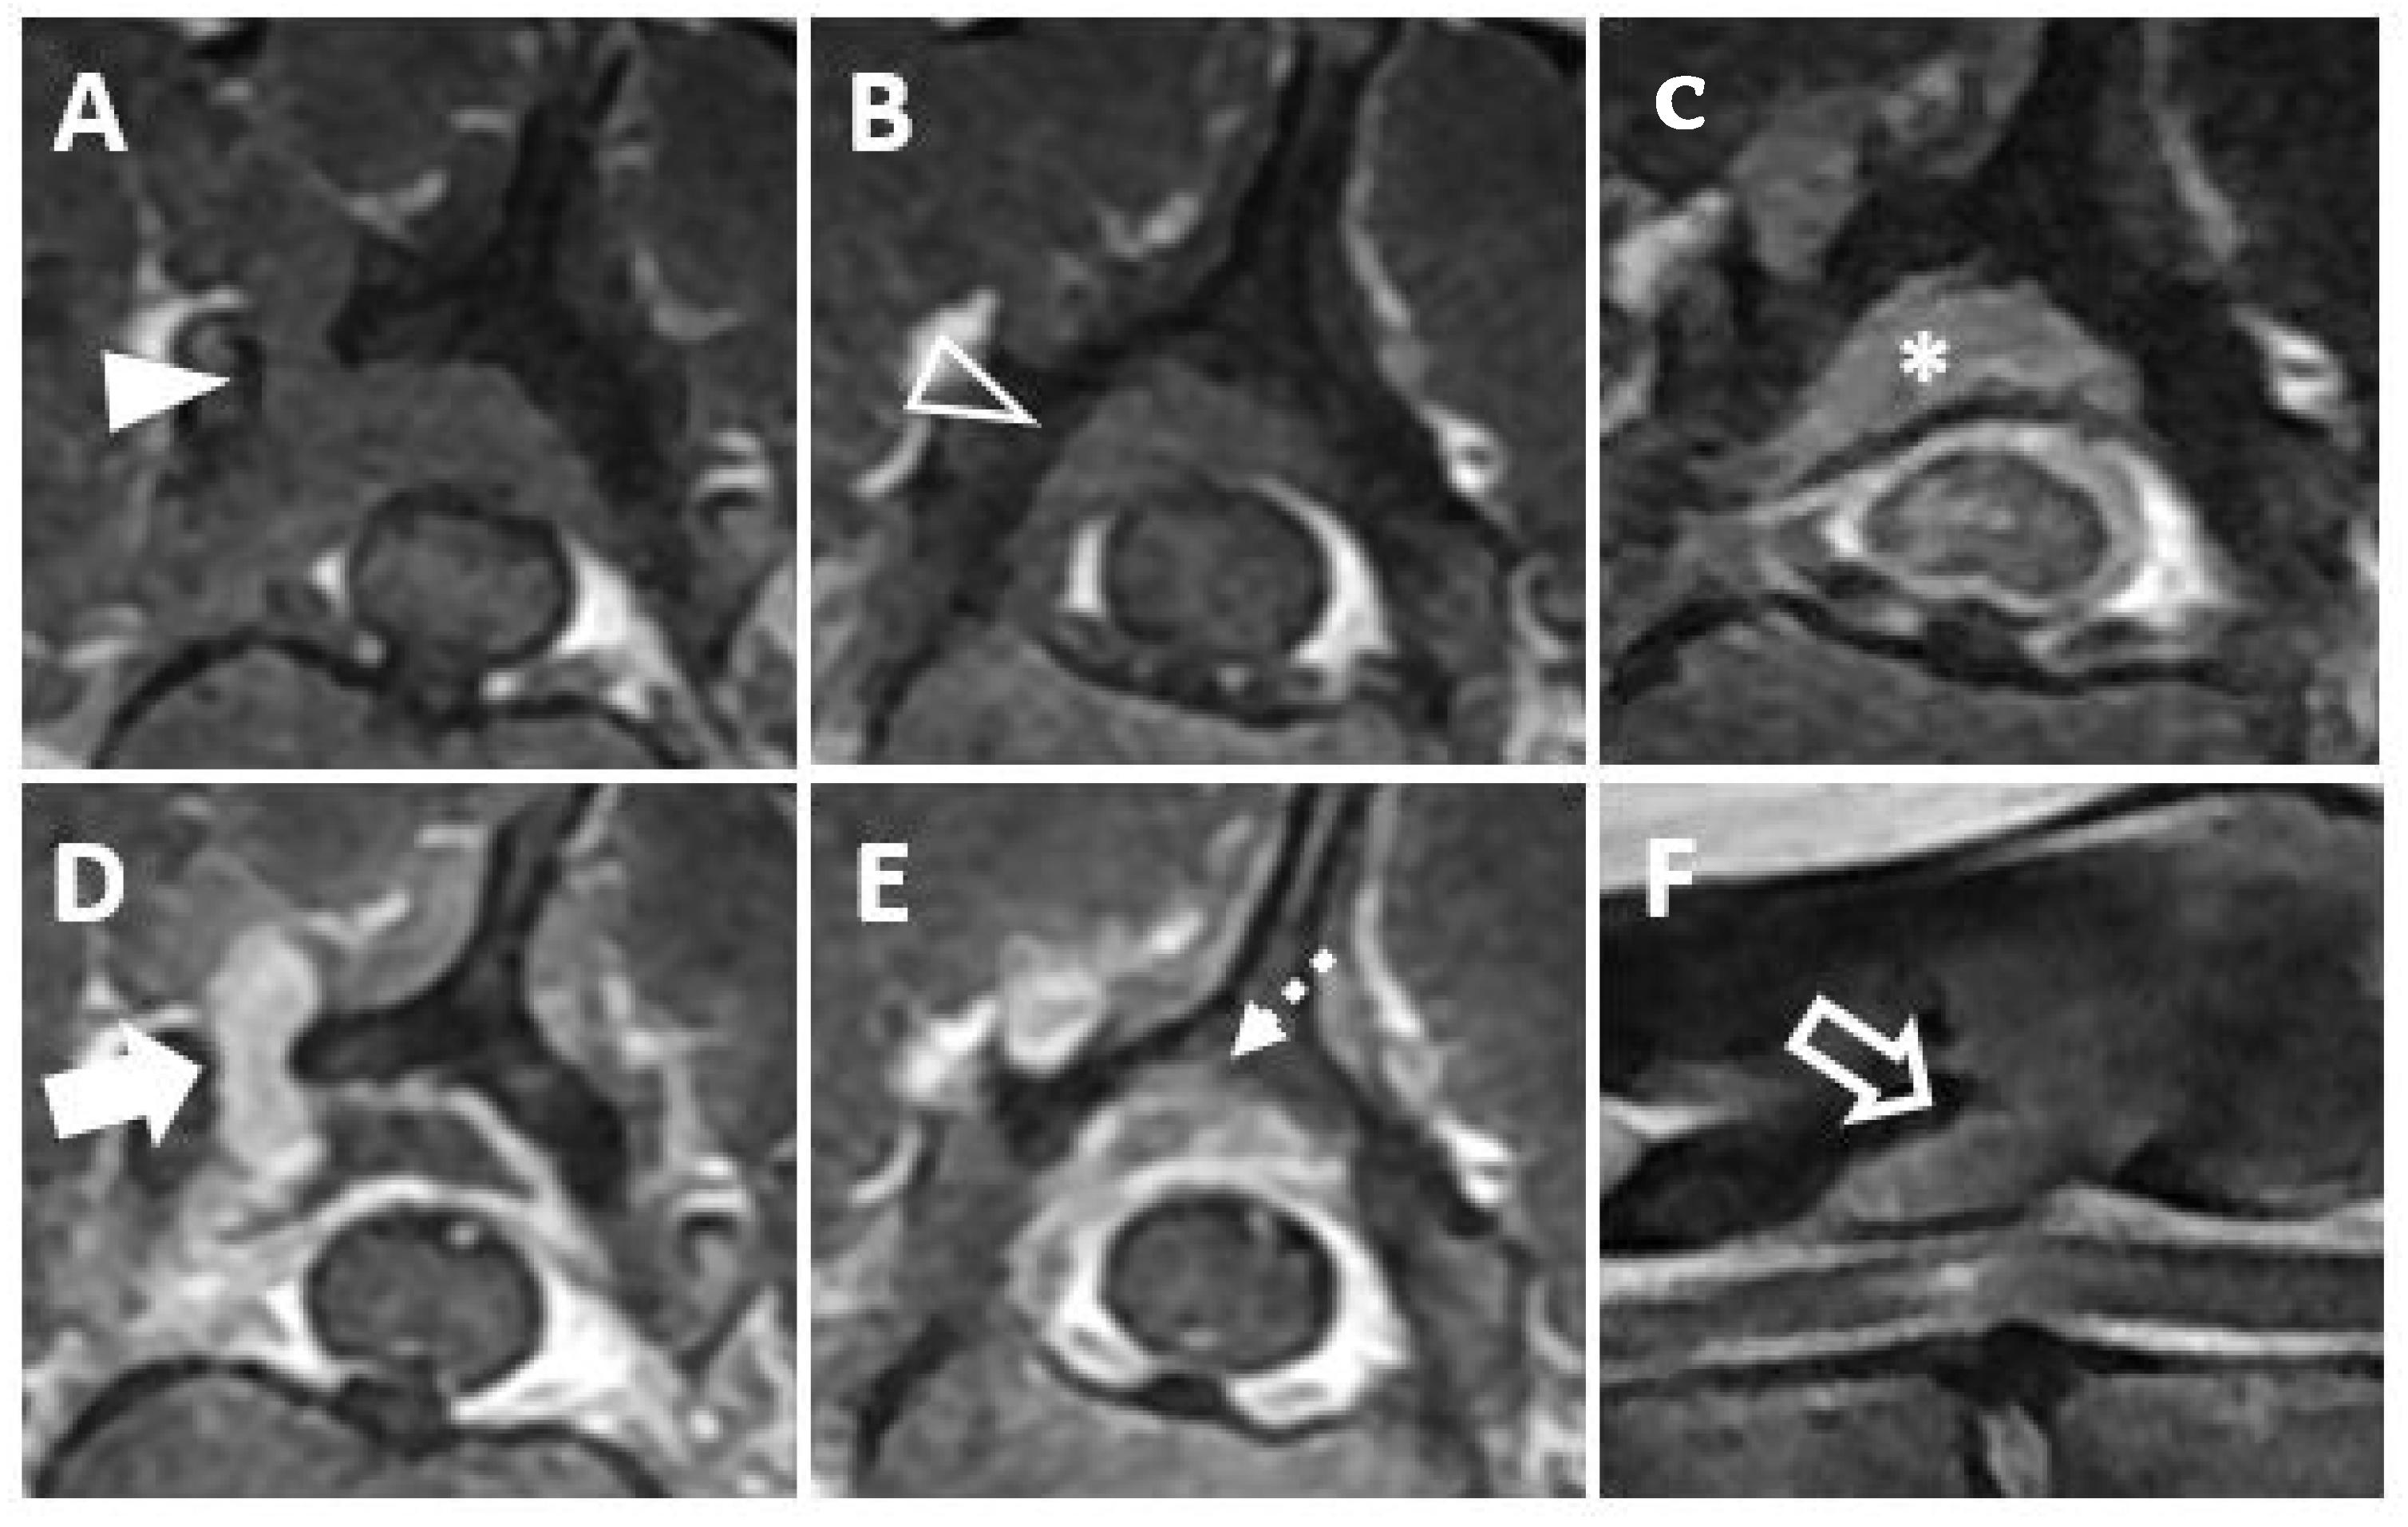

Magnetic resonance imaging (MRI, 1.5T, Signa, GE Healthcare, Waukesha, WI, USA) was performed before and after intravenous administration of a contrast medium (Magnevist; Beyer-Schering Pharmaceutical, Berlin, Germany). The mass was identified at the bone lysis region on a transverse T1-weighted image (Figure 2A) and on a post-contrast, transverse T1-weighted image (Figure 2D). The mass was seen to be invading the vertebral canal on the transverse T1-weighted image (Figure 2B) and on the post-contrast, transverse T1-weighted image (Figure 2E). On the post-contrast, transverse T1-weighted image, the mass was found to be mildly compressing the spinal cord and contrast enhancement of the spinal cord parenchyma was identified, suggesting a mild inflammatory response to the mass (Figure 2C). On a sagittal T2-weighted image, hyperintensity of the spinal cord parenchyma was identified (Figure 2F). Based on CT and MRI findings, an extradural mass invading the vertebral canal was diagnosed. Surgical management of the mass was performed, with the informed consent of the owner, for palliation of hind limb paresis, despite the multiple masses involving pulmonary region.

Figure 2. Magnetic resonance images showing a mass invading the vertebral canal and the spinal cord lesion are depicted. (A The mass appears iso-intense at the bone lysis region on a transverse T1-weighted image (arrowhead). (B) The mass can be seen invading the vertebral canal on a transverse T1-weighted image (open arrowhead). (C) The mass can be seen mildly compressing the spinal cord (asterisk) and contrast enhancement of the spinal cord parenchyma (dashed arrowhead) is visible on a post-contrast, transverse T1-weighted image. (D) Contrast enhancement of the mass (arrow) is shown on a post-contrast, transverse T1-weighted image. (E) The mass can be seen invading the vertebral canal on a post-contrast, transverse T1-weighted image (dashed arrow). (F) The mass (open arrow) between T13 and L1 causing hyperintensity of the spinal cord parenchyma is shown on a sagittal T2-weighted image. (T13: the thirteenth thoracic vertebra, L1: the first lumbar vertebra.).